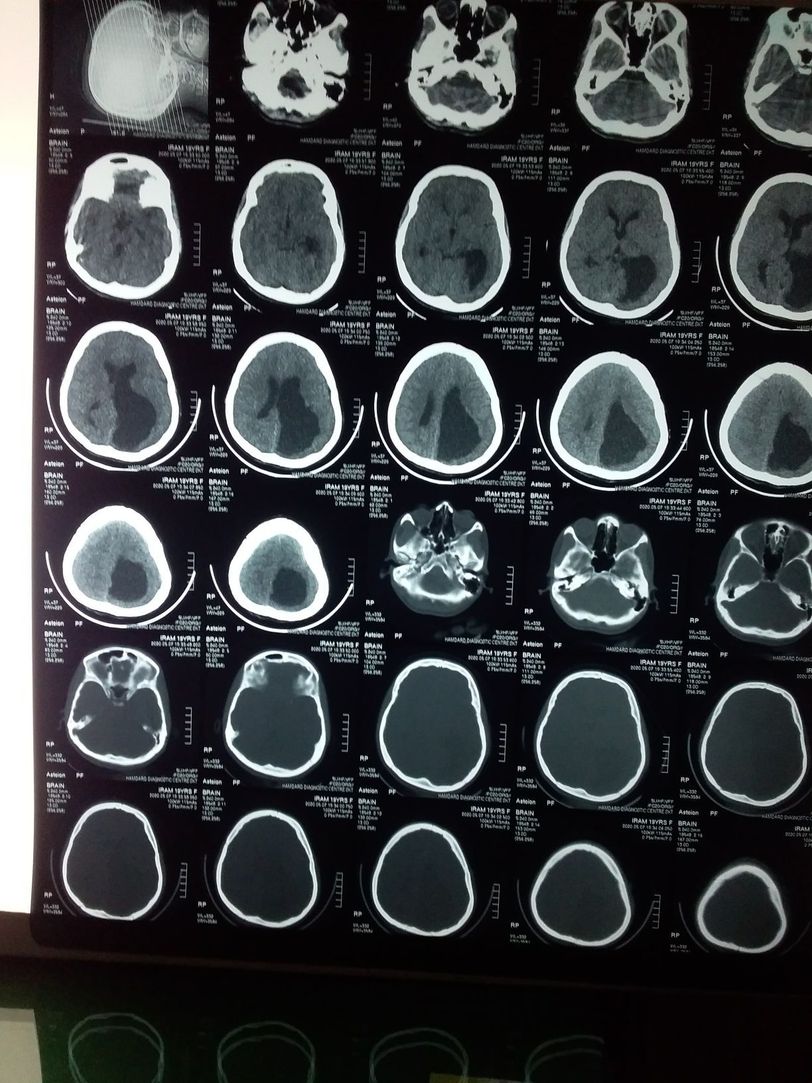

Hx of previous fits. Now come to ER with RTA .

Hydrocephalus

Left hemisphere infract and shifted to right hemisphere